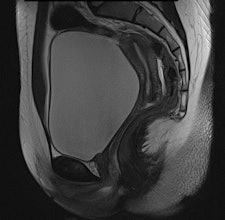

They found BLADE significantly (p < 0.0001) reduced motion and ghosting artifacts and showed improved conspicuity, but overall image quality did not differ significantly in the 47 patients who underwent sagittal BLADE and conventional TSE at 1.5-tesla after glucagon administration. In the majority of cases (53.2% versus 59.6%), radiologists preferred conventional TSE due to better image contrast and visibility of free pelvic fluid. Signal-to-noise ratio (SNR) and contrast-to-noise ratio (CNR) were significantly higher on conventional TSE.

"Indeed, conventional T2-weighted TSE provided a significantly better visibility of free pelvic fluid or cystic structures (i.e., a relatively higher effective T2 weighting) in numerous cases," the researchers noted.

BLADE improves anatomic depiction and image quality thanks to less movement artifact, but at the expense of CNR of cystic structures or visibility of free pelvic fluid.